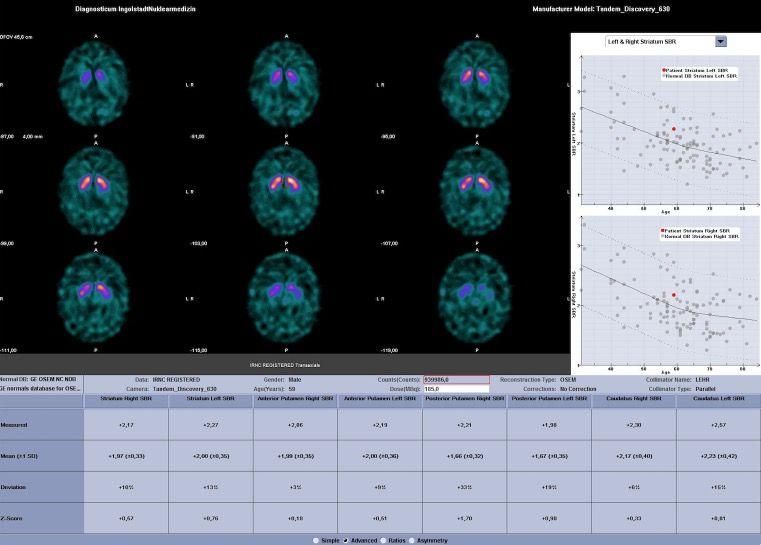

DaTSCAN

Im Vordergrund stehen Untersuchungen der Parkinson-Erkrankungen mit DaTSCAN. Diese radioaktiv markierte Substanz dient der molekularen Bildgebung von Dopamin-Rezeptordichte im Gehirn, wodurch sich Details zur Signalübertragung bildlich darstellen lassen.

Indikation: Unklares Zittern (Tremor) Differentialdiagnose Morbus Parkinson, essentieller Tremor

Bedeutung: Frühdiagnose des Morbus Parkinson